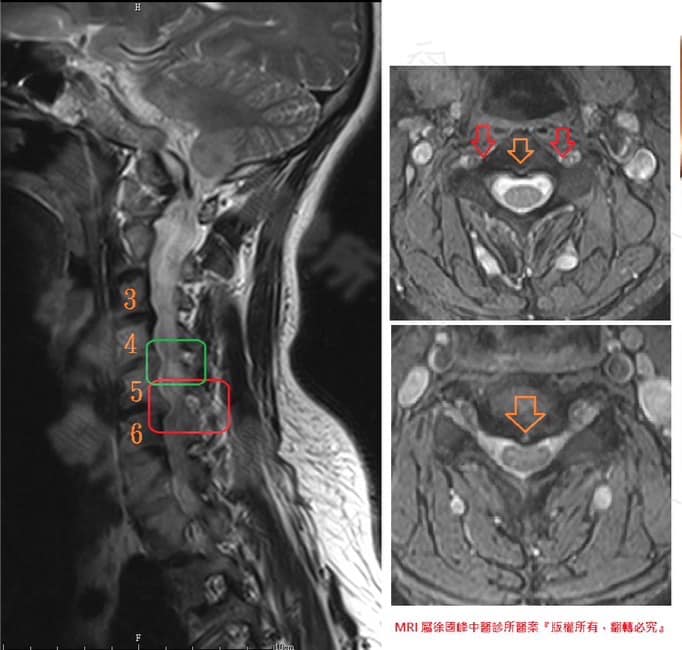

2.C4C5;C5C6 神經根型頸椎病